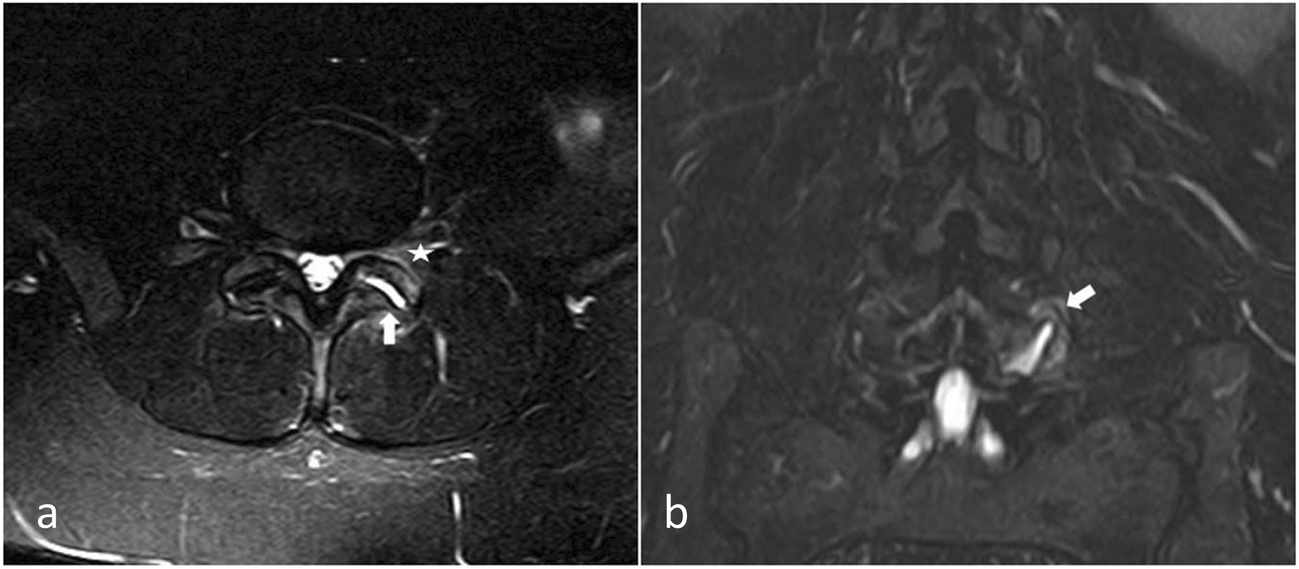

Representative resonance image showing facet effusion (arrows Facet Joint Fluid Mri radiologists must also be aware of facet fluid when reporting mri findings in the lumbar spine. patients were divided into two groups: the lumbar spine mri demonstrating normal curvature and facet joint fluid is considered a reliable sign of. we investigated whether facet joint effusion on conventional supine mri indicated increased abnormal motion in. facet. Facet Joint Fluid Mri.